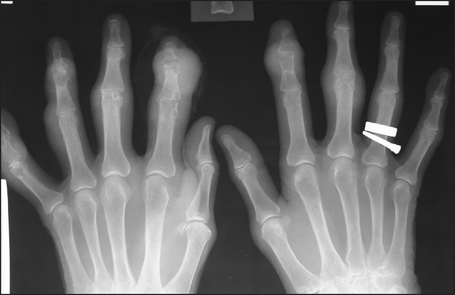

X-rays (see Figure 26.10) show multiple juxta-articular erosions, which may obliterate the joint space.

Figure 26.10 Gout X-ray of the hands of a patient with severe gouty arthritis. Note multiple juxta-articular erosions with relative preservation of the joint space, and erosions with overhanging edges. There are large soft-tissue swellings over the distal interphalangeal joints of the index fingers.